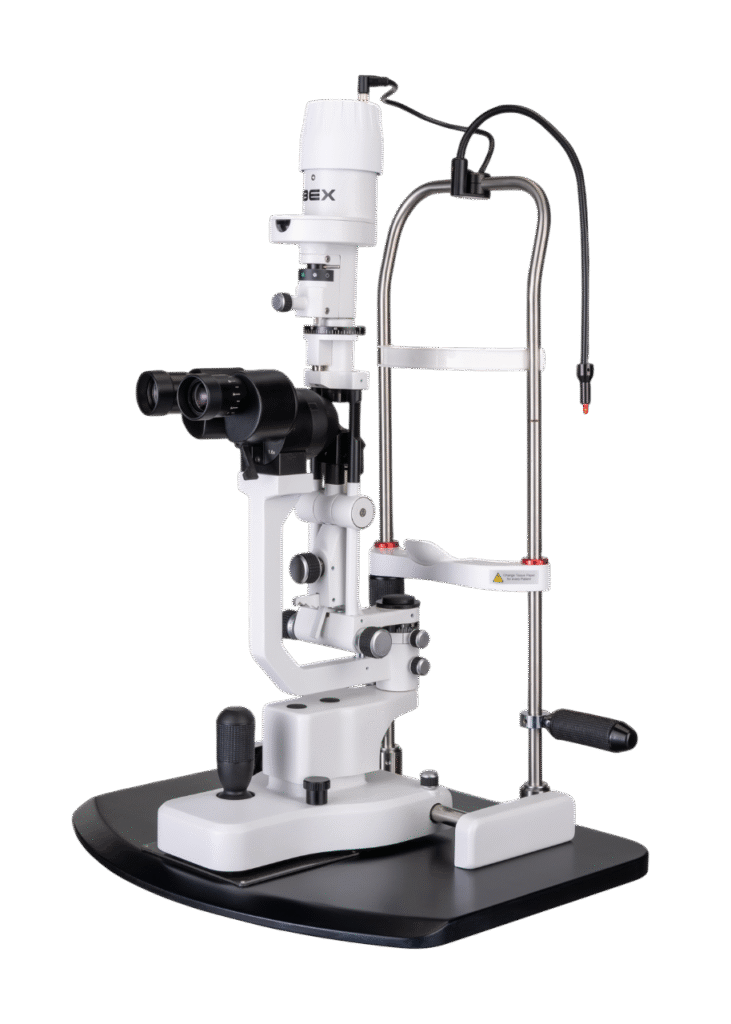

Opteon™ Slit Lamp Imaging + Meibography

Photos & Videos. Clinical Documentation. Patient Education. Reimbursement.

Illuminate your exams and transform patient engagement like never before. When patients see detailed images of their eyes, they gain a deeper understanding of their health and recognize the importance of compliance and follow-up care. Throughout development, our team saw firsthand the profound impact of imaging in the clinic—watching patients smile, express genuine appreciation, and embrace their health journey. That unforgettable experience remains the most rewarding part of our work.

Opteon was born and developed in the clinic, meticulously tested, and perfected through countless hours to ensure that it flows with your exam routine — delivering unmatched reliability and efficiency.

Pushing ahead, our imaging system includes our new, patent-pending Halo background light. Working with native slit lamp illumination, Halo delivers unparalleled clarity of the ocular adnexa. You’ll uncover details of the meibomian glands, acinar spaces, conjunctiva, lid margins, and lashes like never before.